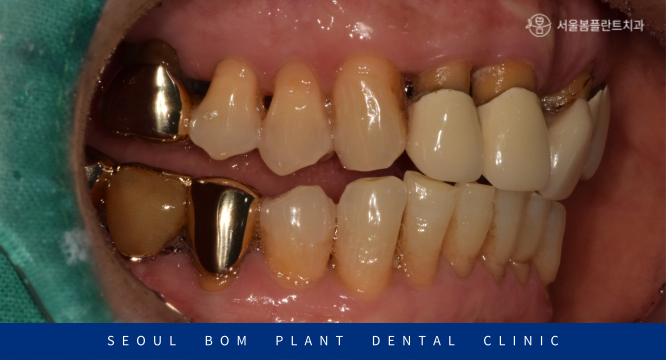

기존 보철물을 제거해 보았더니

위턱 왼쪽 두 번째 앞니(#22)의 치아머리가

이미 파절되어 있는 상태였으며,

발치를 하기에는 아깝다고 판단되어

보철 치료시 보철물 내부의 치아가 너무 약하거나 짧으면

유지력이 떨어질 수밖에 없기 때문에

신경치료를 마무리한 뒤 코아 레진을 이용하여 파절된 치아머리 부분을

단단하게 채워주는 작업을 진행한 뒤 최종 보철물 제작을 위해

필요한 만큼 소량으로 치아 다듬기를 진행하였습니다.